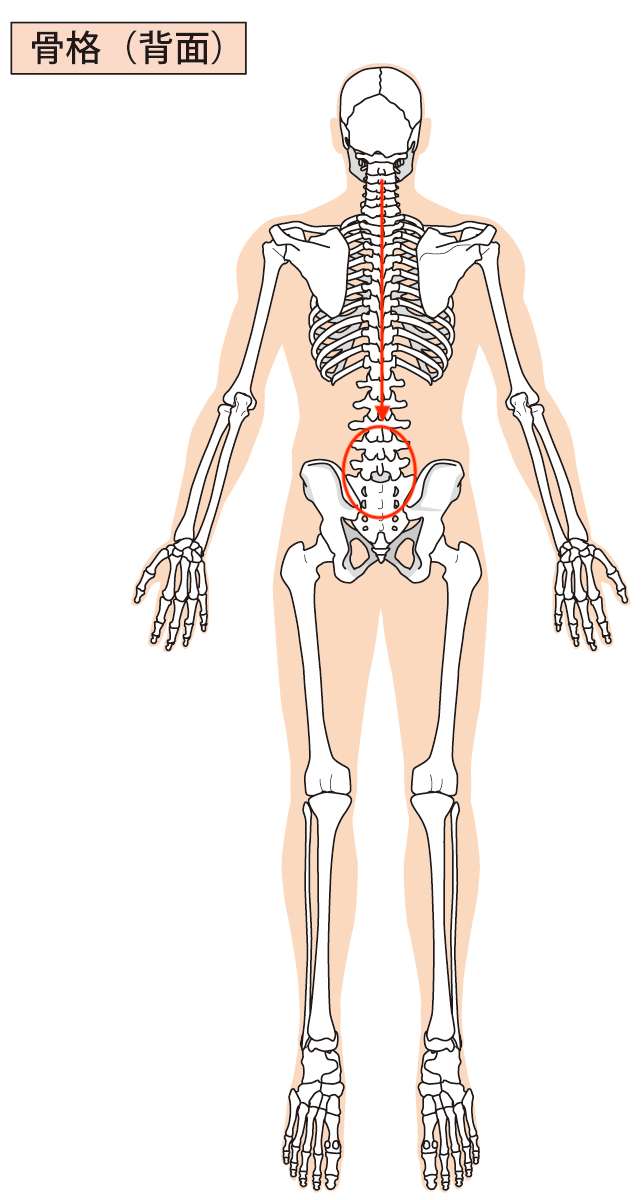

その中で「手のしびれ」に一番影響していたのは、「腰の部分」です。

ご相談いただいた方の体を検査していくと、腰の側から首に対して強い影響力があり、「頸椎ヘルニア」や「変形性頸椎症」もその腰側からの負担である可能性が考えられました。

画像で表すとこういった感じです。

つまり、腰からの負担を首は受ける形となり、首に負担がかかり続けることにより、「手のしびれ」症状につながっていたことがわかりました。

「手のしびれ」症状の元の原因は、腰にあったということになります。